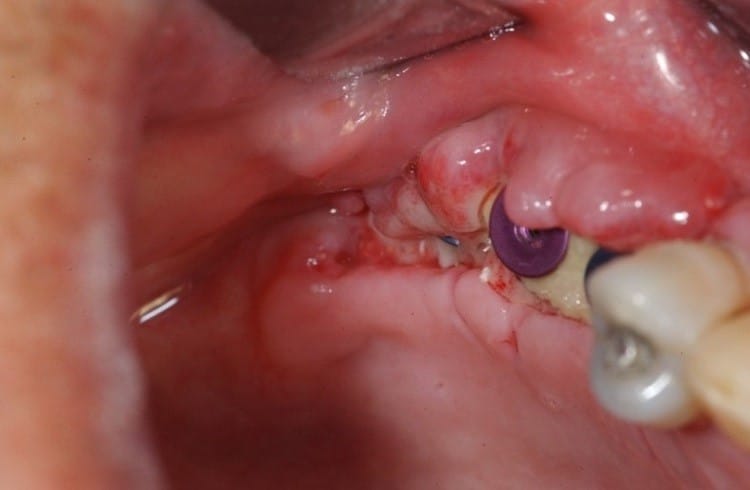

Infection

Infection is one of the early complications that both doctors and patients must be highly cautious about. Symptoms typically include increasing pain instead of decreasing, swelling, redness, discharge, bad odor, or fever. Infection may originate from inadequate sterilization, improper postoperative care, tissue necrosis, or bacterial contamination from food and oral environment.

If detected early and mild, infection can be controlled with medication and hygiene. However, if it spreads or directly affects the bone–implant interface, it may lead to loss of osseointegration and early failure.

Peri-implantitis

This is the most common late complication. It is an inflammatory condition of tissues around the implant, similar to periodontitis around natural teeth. Initially, patients may notice redness, bleeding, bad breath, or food impaction. If untreated, inflammation can extend to bone, causing bone loss.

As bone resorbs, implant support decreases. Patients may feel discomfort, and in severe cases, the implant may become mobile and require removal. Peri-implantitis is often related to poor hygiene, unfavorable prosthetic design, non-optimized abutment, thin soft tissue, or lack of maintenance programs.